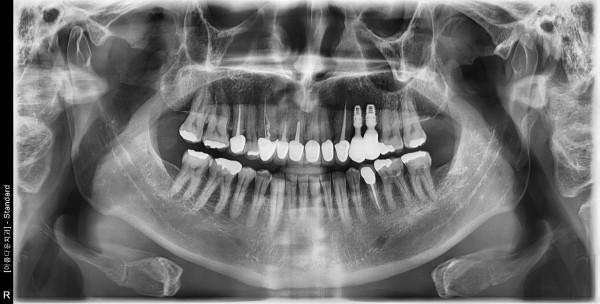

50세 남/ 상악 좌측 소구치 발치 및 치조골 이식술 후 임플란트 식립